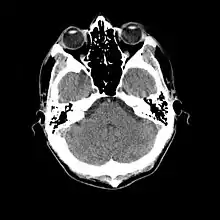

More recently, computed tomography has played a large role in reconstructing endocasts. The procedure is non-invasive and has the advantage of being able to analyze a fossil in record time with little risk of damaging the fossil under review. CT imaging is achieved through the application of x-rays to produce tomographs, or sectional density images, which are similar to the images produced during MRI scans.[8] CT scans use slices approximately 1 mm thick to reconstruct a virtual model of the specimen.[9] This method is especially useful when a fossil cranium is occupied by a natural endocast that cannot be removed without destroying the skeletal portions of the fossil. Because the cranium and its contents are of different densities, the endocranial cavity and its unique traits can be reconstructed virtually.[8]

Radiographic technique such as computed tomographic imaging, or CT scans, coupled with computer programming have been used to analyze brain endocasts from as early as 1906.[10] Recent development of advanced computer graphics technology have allowed scientists to more accurately analyze of brain endocasts. M. Vannier and G. Conroy of Washington University School of Medicine have developed a system that images and analyzes surface morphologies in 3D. Scientists are able to encode surface landmarks that allows them to analyze sulcal length, cortical asymmetries and volume.[11] Radiologist, paleoanthropologists, computer scientists in both the United States and Europe have collaborated to study such fossils using virtual techniques.[10]